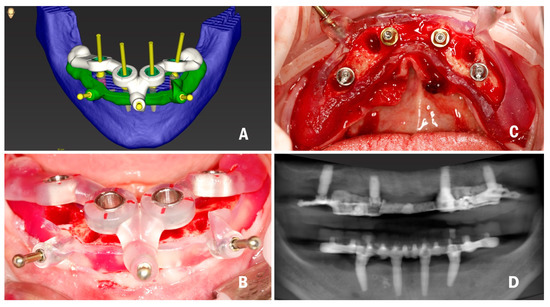

To address the research purpose, the authors designed this study, which was conducted at the university clinic, and was approved by the Institution review board of the Department of Oral and Maxillo-Facial Sciences, “Sapienza” University of Rome (Ref: 038/2020). A 60-year-old male was selected to be included in this study, after attending the university clinic for implant treatment. The patient was in good health, displaying good oral hygiene (full mouth plaque score and full mouth bleeding score <25%), no need for guided bone regeneration procedures, an absence of uncontrolled systemic diseases, a nonsmoker, and no signs of acute local inflammation at the time of implant placement. He had a failing dentition (critical loss of attachment, nonrestorable teeth, fractured teeth, root caries) in the mandible, with four mobile incisors that could not be used as a support for a surgical template, which created difficulties for correct matching, and a very narrow ridge in the frontal area. These factors predetermined the stackable bone-supported surgical template design for this patient. Radiopaque 3D markers were attached to the existing prosthesis to also serve as a radiographic template prior to CBCT acquisition. The denture was further relined with soft material (GC Soft Liner) before the acquisition of the CBCT scan, thus avoiding possible prosthesis movement and for the precise transition of the actual soft tissue of the patient in the planning software. The first CBCT was performed on the patient with Green 16 (Vatech, Fort Lee, NJ, USA) in standard conditions (94 kVp, 8.0 mA, 360° rotation, 9 s, FOV: 100 x 85, voxel size: 200 μm) with the mouth closed, as separating the arches could cause radiological template movement. A protocol described by Storelli et al. [27] was implemented: after CBCT acquisition, an STL file of the denture was obtained using the laboratory scanner (Straumann 7 series lab scanner, Institut Straumann AG, Basel, Switzerland). Data obtained in digital imaging and communications in medicine (DICOM) format were then imported into a surgical planning software (coDiagnostiX, Institut Straumann AG). All of the acquisition parameters that could influence the accuracy of later steps in the generation of a virtual model, such as segmentation, as described by Shujaat et al. [28], were assessed. Data in standard tessellation language (STL) format were imported into the software to prosthetically orient implant positions. CBCT data of the patients in DICOM (Digital imaging and communications in medicine) format and STL files of radiographic templates of edentulous patients were matched in the surgical planning software. Four conical dental implants (BLT, Institut Straumann AG) with a sandblasted/long-grit/acid-etched surface (SLActive) were planned for prosthetically-oriented positions at 35, 32, 42, 45 sites: two 4.1 mm × 10 mm for the premolar sites and 3.3 mm × 12 mm for the incisor sites, in accordance with the Straumann Pro Arch protocol, which consists of dental implant and SRA (screw-retained abutment) placement with immediate loading. A bone-supported surgical template with a stackable design was chosen to increase the predictability of bone reduction [29], as the patient had a very narrow ridge coronally in the frontal area, which needed to be reduced to obtain the appropriate width for implant placement. The first part of the surgical template was bone-supported and was designed to guide bone reduction. It was designed on the base of the segmentation converted to the STL file. The template was stabilized to the bone with two lateral fixation pins. The second part of the surgical template was positioned on top of the bone reduction template and served in implant placement. Several techniques to connect two different surgical templates are described in the literature, such as the use of magnets [30]. In the present study, the authors describe a more cost- and time-efficient technique. The second part of the surgical template was fixed to the first template with the locks designed on both using the inspection window tool, and the third lateral fixation pin was stabilized either to the first part of the stent or to the bone (Figure 1A).

Figure 1.

(A) Computer-assisted implant planning; (B) Implant placement surgery; (C) Implants and SRA in situ; and (D) Postoperative CBCT.

The virtual bone reduction was then performed in the software and a segmentation of the residual bone was created. To minimize factors relating to 3D printing that could affect accuracies, such as template-to-teeth offset or sleeve-to-template offset, the calibration matrix was 3D printed and the 3D printer and printing material were calibrated. The surgical template was then three-dimensionally (3D) printed.

One hour before surgery, prophylactic antibiotics, 2 gr of amoxicillin (Zimox, Pfizer), were given to the patient. The flap was raised, and the first template was positioned; osteotomies for pins were made and the template was fixed with lateral fixation pins. The bone reduction was performed with the piezoelectric instrument VarioSurg (NSK/Nakanishi, Japan). The second template for implant placement was positioned on top of the first one and fixed with the third pin. Osteotomies were performed through the surgical template following the protocol derived from the software (Figure 1B). Then, the dental implants were inserted by properly following the manufacturer’s instructions and the surgical insertion protocol. All implants reached a minimum insertion torque of 35 Ncm, so the SRA were tightened to the implants at 35 Ncm with a surgical motor with torque control (SurgicPro+, NSK/Nakanishi, Japan) (Figure 1C). Impressions were made with polyvinyl siloxane (Elite, Zhermack), the prosthesis was finalized in the laboratory, polished, and immediate loading was performed. The prosthesis was delivered to the patient after occlusion checking, tightening the screws at 15 Ncm, and sealing the screw access holes with polytetrafluoroethylene (PTFE) tape and a flowable composite resin. After 3 months, the temporary prosthesis was unscrewed for the first time to check implants osteointegration, which was uneventful and successful. The patient received a screw-retained titanium bar with resin veneering as the definitive prosthesis. The actual follow-up period is set for 3 years.